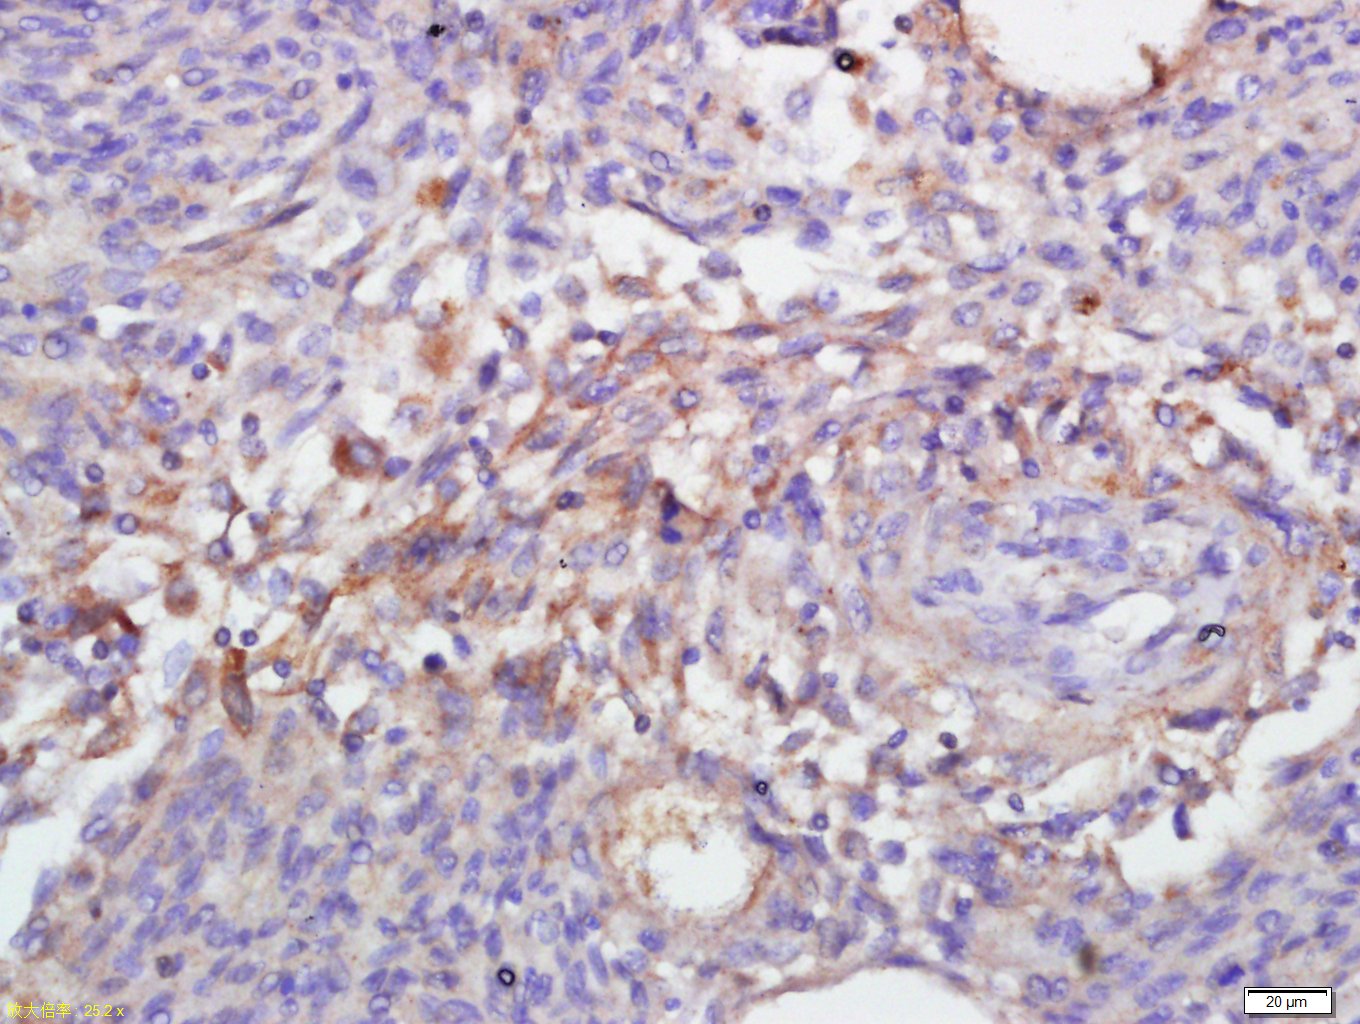

Tissue/cell: human Neurological glioblastoma; 4% Paraformaldehyde-fixed and paraffin-embedded; Antigen retrieval: citrate buffer ( 0.01M, pH 6.0 ), Boiling bathing for 15min; Block endogenous peroxidase by 3% Hydrogen peroxide for 30min; Blocking buffer (normal goat serum,C-0005) at 37← for 20 min; Incubation: Anti-Annexin V Polyclonal Antibody, Unconjugated(bs-0450R) 1:500, overnight at 4⒉C, followed by conjugation to the secondary antibody(SP-0023) and DAB(C-0010) staining

Tissue/cell: rat testis tissue; 4% Paraformaldehyde-fixed and paraffin-embedded; Antigen retrieval: citrate buffer ( 0.01M, pH 6.0 ), Boiling bathing for 15min; Block endogenous peroxidase by 3% Hydrogen peroxide for 30min; Blocking buffer (normal goat serum,C-0005) at 37← for 20 min; Incubation: Anti-Annexin V Polyclonal Antibody, Unconjugated(bs-0450R) 1:500, overnight at 4⒉C, followed by conjugation to the secondary antibody(SP-0023) and DAB(C-0010) staining